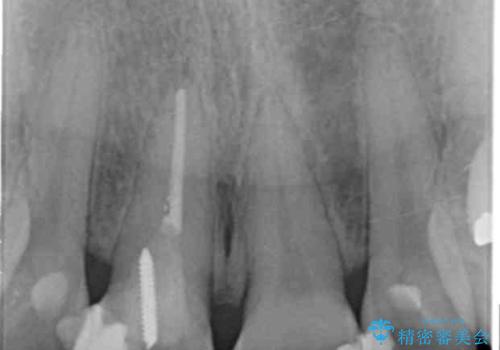

- 「 以前神経を取った歯の変色が気になる。前歯をきれいにして欲しい。」と治療を希望され来院されました。

目立つ上顎前歯に変色・大きな虫歯治療痕が見られ、審美障害を引き起こしています。

虫歯の徹底的な除去、根管治療を行いセラミック治療に入る前の環境をしっかりと整えたのち審美的なジルコニアセラミックで治療を仕上げました。